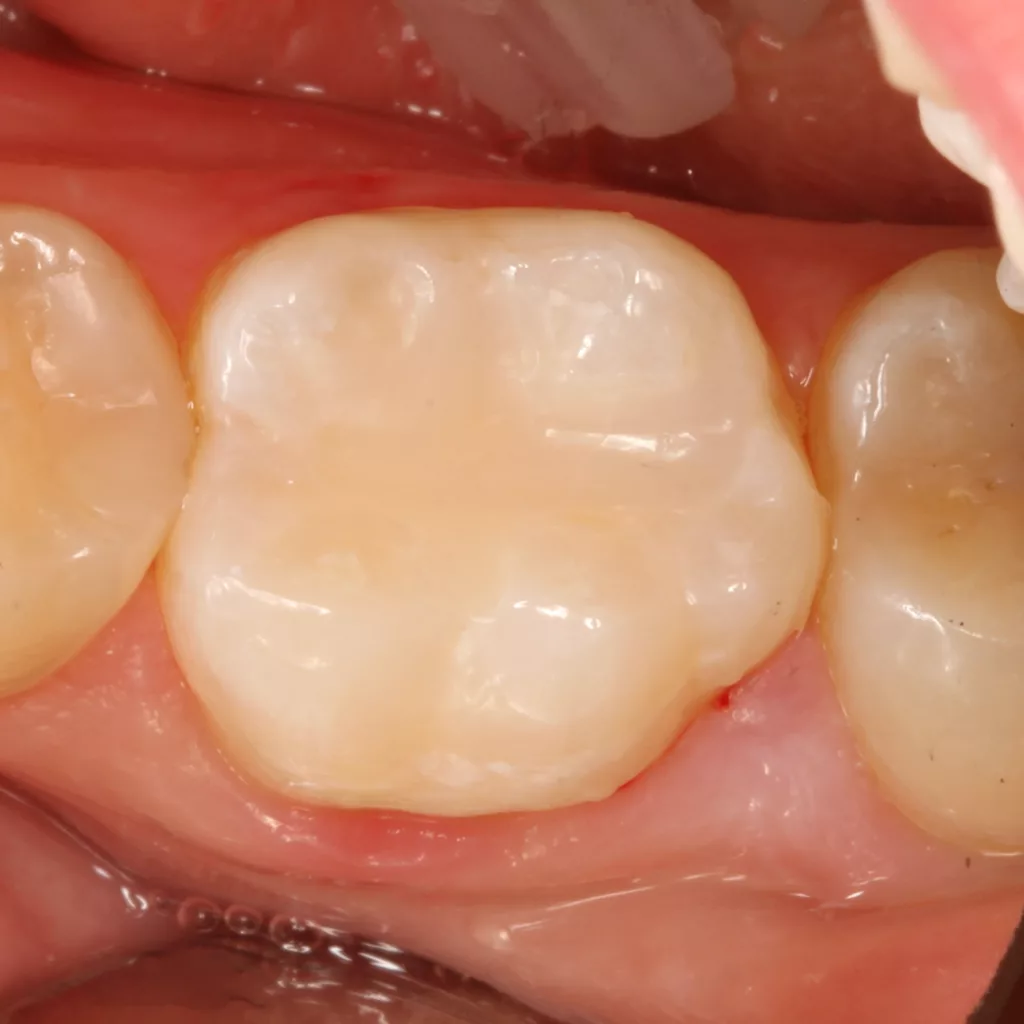

Fall 1: Versorgung einer Initialkaries an Zahn 45

Bei der 54 Jahre alten Patientin fiel eine versteckte Approximalkaries distal an Zahn 45 auf (Abb. 1). Nach Eröffnung des Defektes (Abb. 2) zeigte sich das Ausmaß des stark unterminierenden Defektes. Nach vollständiger Kariesexkavation, Präparation des Defektes und Ausformung der Kavität mit einer Teilmatrize (Danville ultra thin flex, Zest Dental Solutions, CA, USA), einem Kunststoffkeilchen (G-Wedge, Garrison, MN, USA) und einem NiTin-Prämolaren-Spannring (re-invent Dental Products GmbH, Abb. 3) erfolgte erneut unter relativer Trockenlegung nach adhäsiver Vorbehandlung (G2 Universal, GC, total etch) die Versorgung mit dem niedrigviskösen Visalys Bulk Flow – diesmal in einem einzigen Inkrement (Abb. 4). Das Material ließ sich nach der Applikation mit einer Sonde ausformen und die Randleiste durch Verstreichen an der Innenseite der Matrizenfolie so gut darstellen, dass nach Abnahme der Matrize kaum noch Ausarbeitungsaufwand bestand.

Die Polymerisation erfolgte zunächst für 20 Sek. aus okklusaler Richtung (Elipar Deep Cure, 3M), nach Abnahme der Matrize erfolgten zwei weitere Härtungszyklen für nochmals 20 Sek.: einmal aus bukkaler Richtung sowie ein Nachhärten der Restauration mit mittig okklusal auf dem Zentrum der Füllung platziertem Lichtaustrittsfenster. Die Abbildung 5 zeigt die Restauration unmittelbar nach Ausarbeitung und Politur (Diacomp Plus Twist, EVE). Die sehr gute Farbanpassung beeindruckt: Das Material erscheint auf keinen Fall zu transluzent, obwohl es in einer 4-mm-Bulkanwendung eingesetzt worden war. Durch die Versorgung des kleinen Defektes in einem einzigen Inkrement reduziert sich neben der Arbeitszeit auch das Risiko einer nicht bemerkten Defektstelle zwischen Einzelinkrementen bei derart schwer einseh- und kontrollierbaren Kavitäten. Das Ergebnis spricht unter ästhetischen und funktionellen Aspekten für sich. Die Abbildung 6 zeigt die klinische Situation bei einer Nachkontrolle nach sechs Monaten: Es sind weder Randverfärbungen noch Desintegration erkennbar, die Ästhetik ist unverändert.